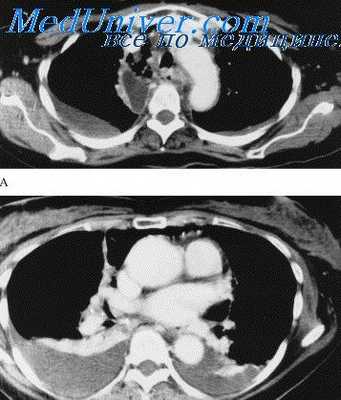

Основной опасностью при такой операции является возможность повреждения больших вен. Струма отодвигает левую плечеголовную вену (безымянную вену) кпереди и поднимает ее в вентральном направлении. Уже во время проведения стернотомии следует думать о том, что эта вена расположена сразу за грудиной. Правая плечеголовная (безымянная) вена отодвигается струмой вправо, при этом она сильно изгибается и образует дугу того же направления. При выделении струмы легко повреждаются расширенные и извитые венозные коллатерали. Нижняя щитовидная артерия может простираться далеко вглубь средостения вдоль шейного и медиастинального ложа через перемычку, соединяющую эти два отдела струмы.

Струма, опускаясь от шеи в средостение, простирается впереди больших сосудов (преваскулярно), редко сзади этих сосудов (ретроваскулярно). Как правило, струма асимметричной формы, так как с левой стороны дуга аорты ограничивает ее распространение. Поэтому чаще всего наибольшая часть струмы располагается справа от грудины. Она нередко кольцом охватывает торакальную часть трахеи и распространяется между трахеей и пищеводом. При мобилизации ретроваскулярно расположенной струмы можно легко повредить проходящий справа возвратный нерв, который проходит вокруг подключичной артерии в месте ее выхода из плече-головного ствола.